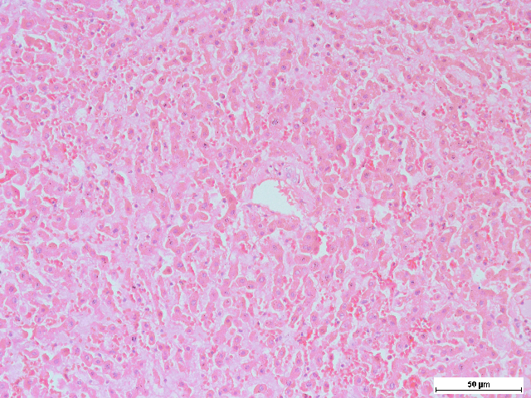

Swollen and shrinking of hepatocytes, with occasional cytoplasmic eosinophilia, Note that the sinusoids were widened